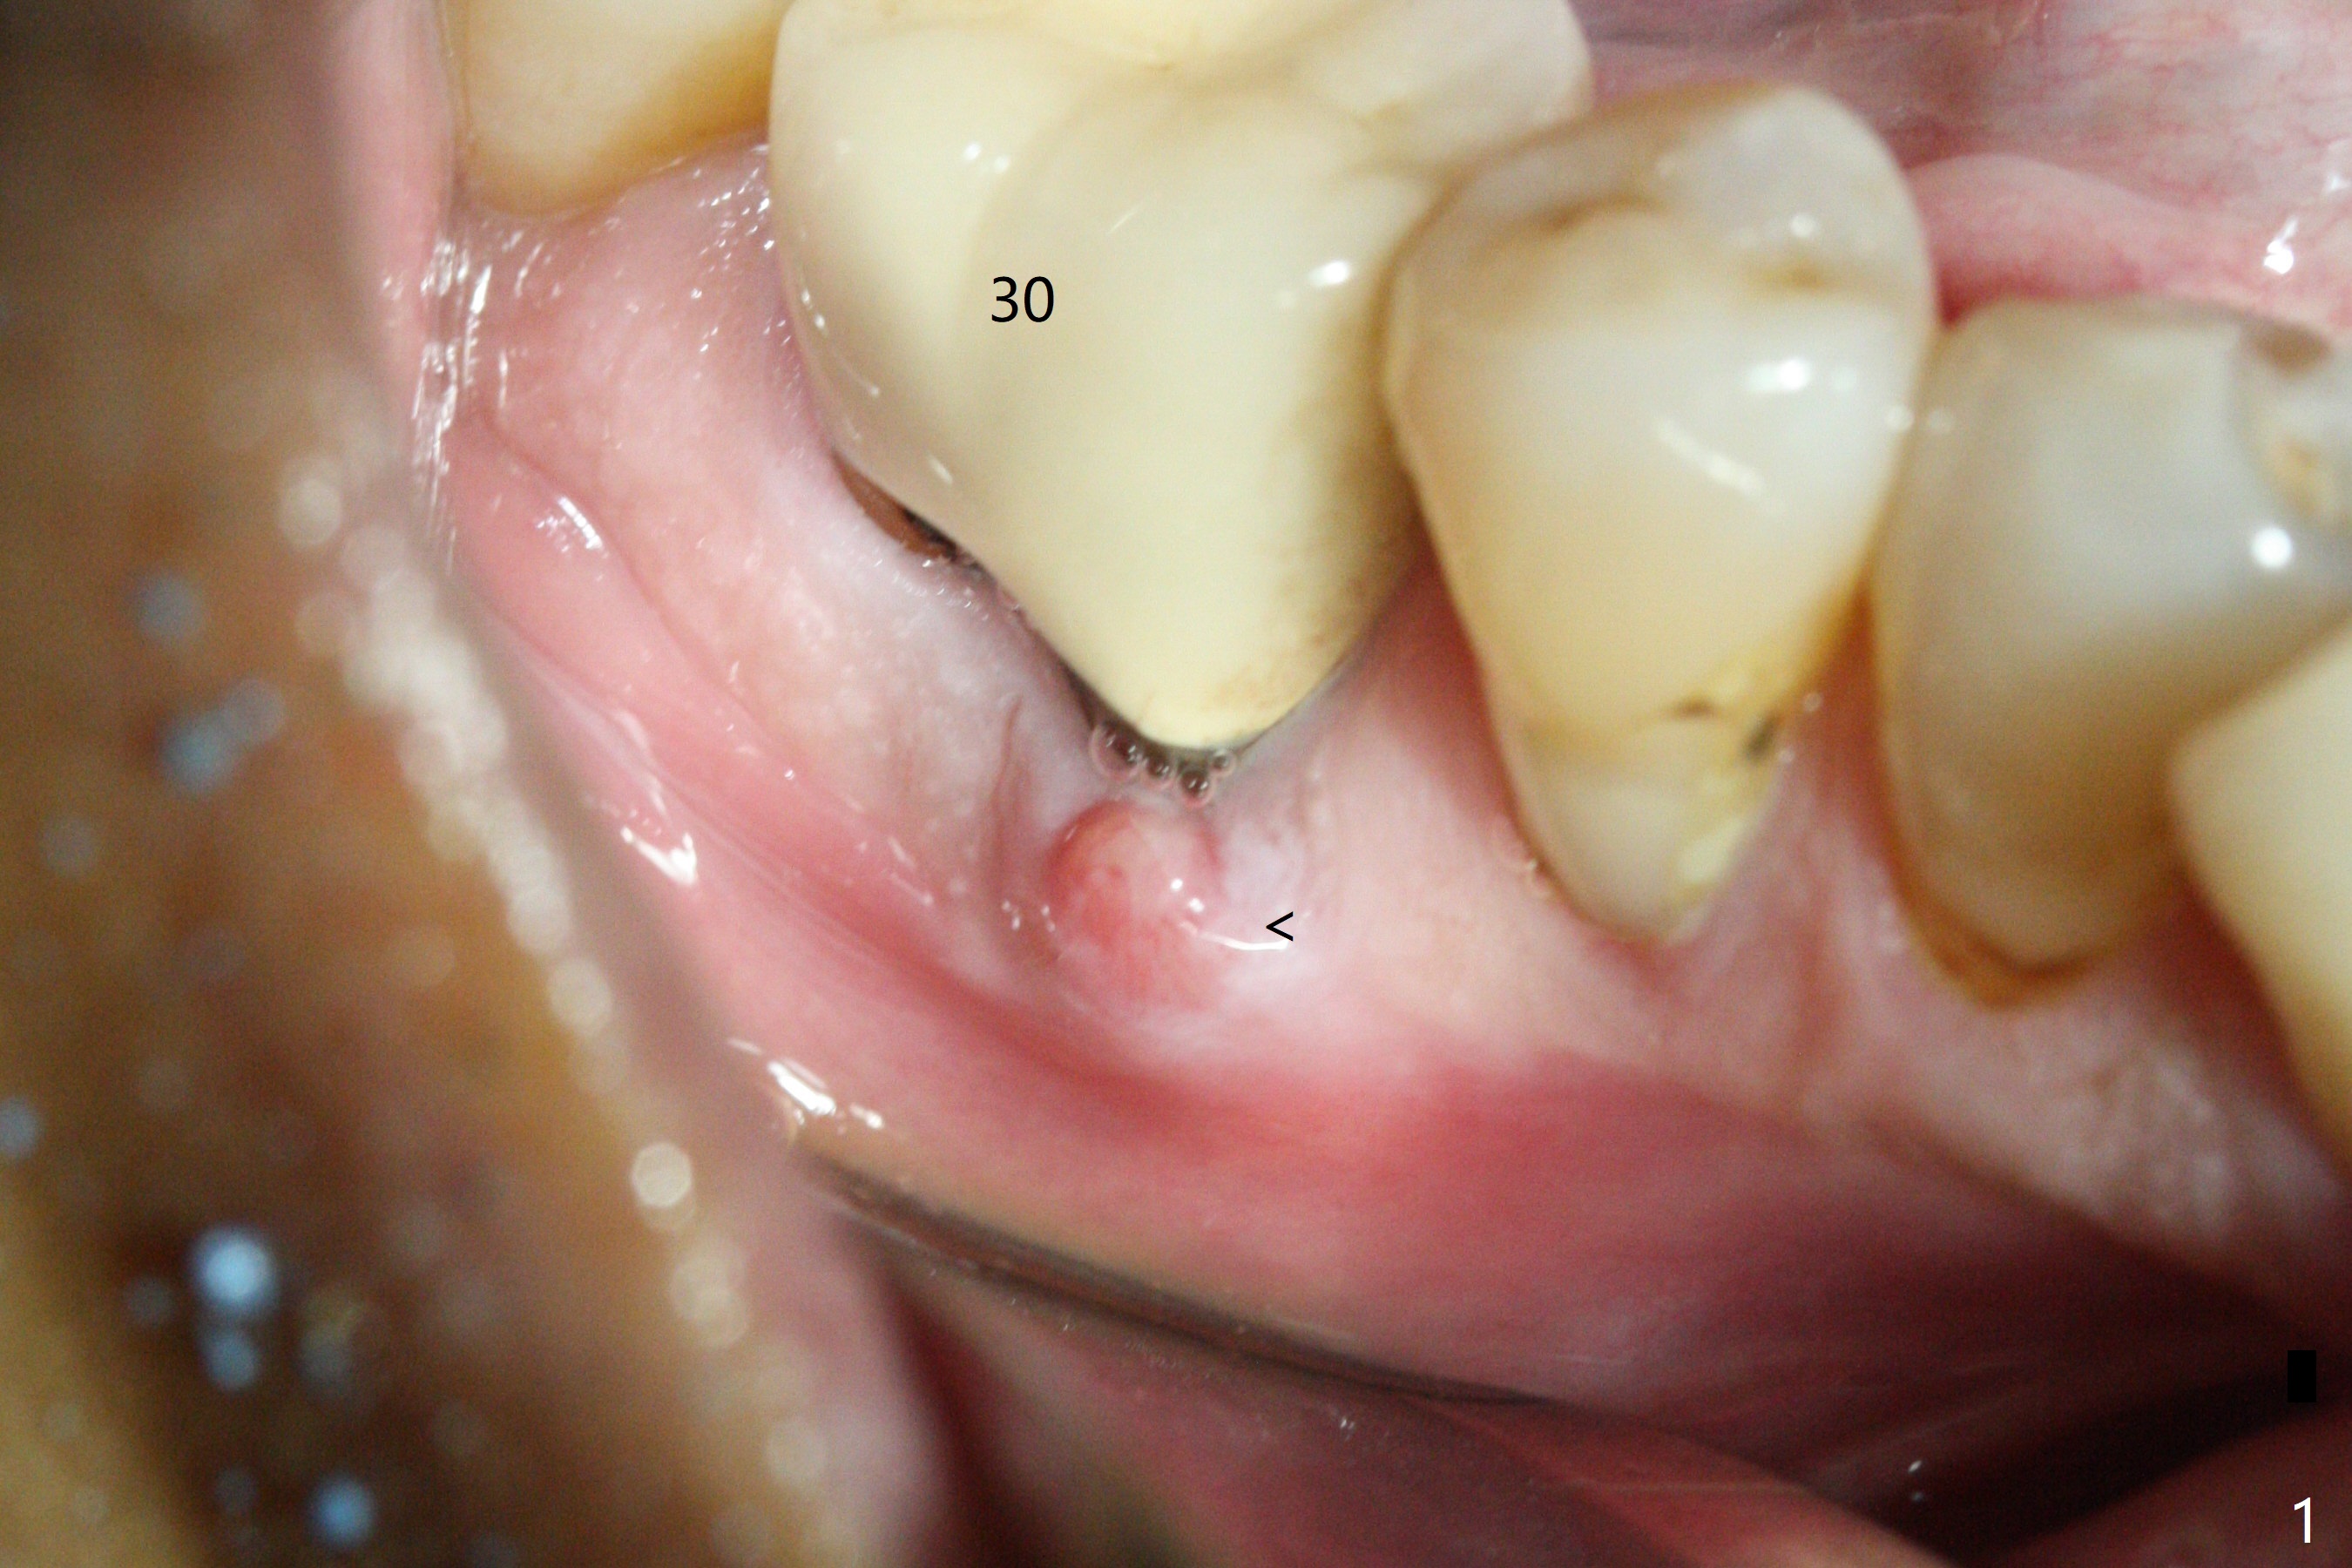

After extraction of the tooth #30, the mesiobuccal plate is found to be lost, corresponding to the fistula (Fig.1 <). Osteotomy is initiated in the flattened septum (lingual) for 13 mm (Fig.2). The patient feels pain when larger drills are being used. Marcaine has to be injected in an infiltration manner for pain control. When a 4.5x10 mm dummy implant is inserted with 55 Ncm, the end of the osteotomy (Fig.3 white line) is close to the Inferior Alveolar Canal (red dashed line). When a definitive implant (Fig.4: 4.5x11.5 mm) is placed with primary stability, there is an apical space (Fig.5 white double arrows). There is moderate postop pain. A shorter implant (10 mm) should be tried when the bone is dense. It will be associated with less pain. The fistula disappears 7 days postop (Fig.6). Although the patient appreciates that the pain is gone, there is atrophy mesiobuccally 2 months postop (Fig.7 *). The implant seems to be have been placed too buccally (Fig.8). With loss of the buccal plate, the implant should be placed away from it to prevent periimplantitis. The abutment is changed from 6.5x4(4) to 6.5x5.5 (3) mm with fabrication of a new provisional. The buccal margin is still supragingival 6 months postop and prep lower before impression. The mesial and distal sockets appear to have healed (Fig.9). When the crown is cemented, the mesiobuccal papilla is present (Fig.10 *), while the mesiolingual one is apparently absent (Fig.11 *). Using a temporary abutment and relining the provisional multiple times would increase the chance of rebuilding the missing papilla. The bone density around the implant increases 11 months post cementation (Fig.12). The dense (apparently cortical) bone seem to grow over the implant plateau 11 months post cementation (Fig.13 <).